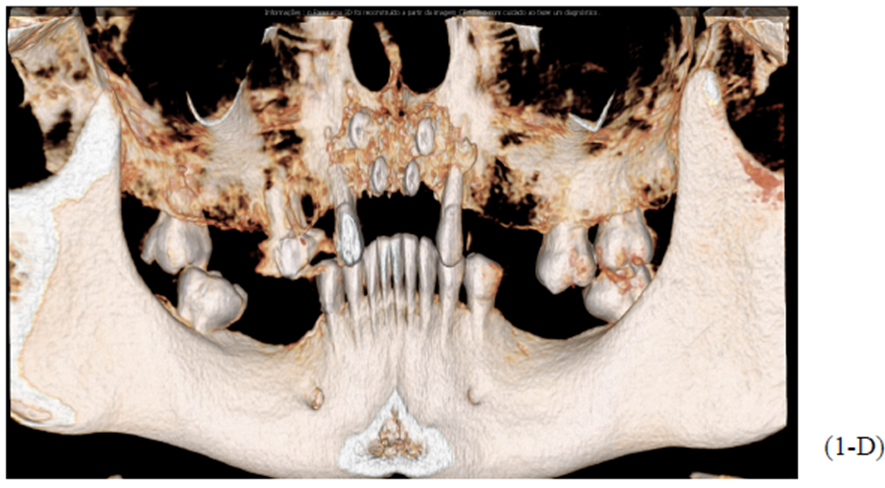

Após oito meses, foi realizada outra tomografia computadorizada (TC) na própria clínica escola, onde foram realizadas medidas de altura e espessura evidenciando grande ganho ósseo horizontal. Não ocorreu quaisquer tipos de complicação no pós-operatório tardio. (Figuras 1-A, 1-B, 1-C, 1-D).

Foram planejados quatro implantes do tipo Cone Morse Maestro Implacil De Bortoli 3.5 x 11 mm. Após remoção de maneira facilitada dos parafusos tenda, foram instalados quatro implantes em ótimo posicionamento tridimensional como evidencia as Figuras 1-E, 1-F, 1-G e 1-H). Todos apresentaram estabilidade primária de 35 Ncm de torque, e aguardamos quatro meses para posterior reabilitação protética definitiva com próteses metalocerâmicas individualizadas do tipo parafusada.